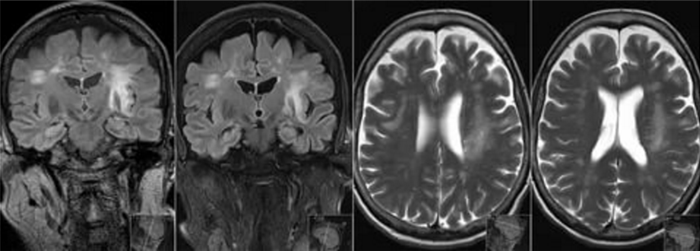

- МРТ головного мозга. Обнаруживается диффузная мультифокальная демиелинизация, очаги имеют различный размер, асимметрично располагаются в белом веществе, таламусе, базальных ядрах.

о Мультифокальные гиперинтенсивные на Т2-ВИ бляшки демиелинизации, поражающие субкортикальное белое вещество (БВ) и распространяют на глубокое БВ; серое вещество часто остается сохранно вплоть до поздней стадии заболевания О Обычно двустороннее, но асимметричное поражение; контрастное усиление или масс-эффект отсутствуют о Поздняя стадия: сливные зоны поражения БВ с кистозными изменениями

• Т2-ВИ: зоны гиперинтенсивного сигнала с преимущественной локализацией в субкортикальном и перивентрикулярном БВ:

• FLAIR: зоны гиперинтенсивного сигнала в субкортикальном и перивентрикулярном БВ

МРТ-картина характеризуется широко распространенными демиелинизирующими очагами, локализованными в полушариях головного мозга, но иногда в стволе головного мозга и мозжечке и редко в спинном мозге. Очаги сильно варьируют по размеру: от микроскопических очажков демиелинизации до массивных мультифокальных зон деструкции миелиновых и аксоновых цилиндров, вовлекающих большую часть полушария головного мозга или (как было указано выше) мозжечка.